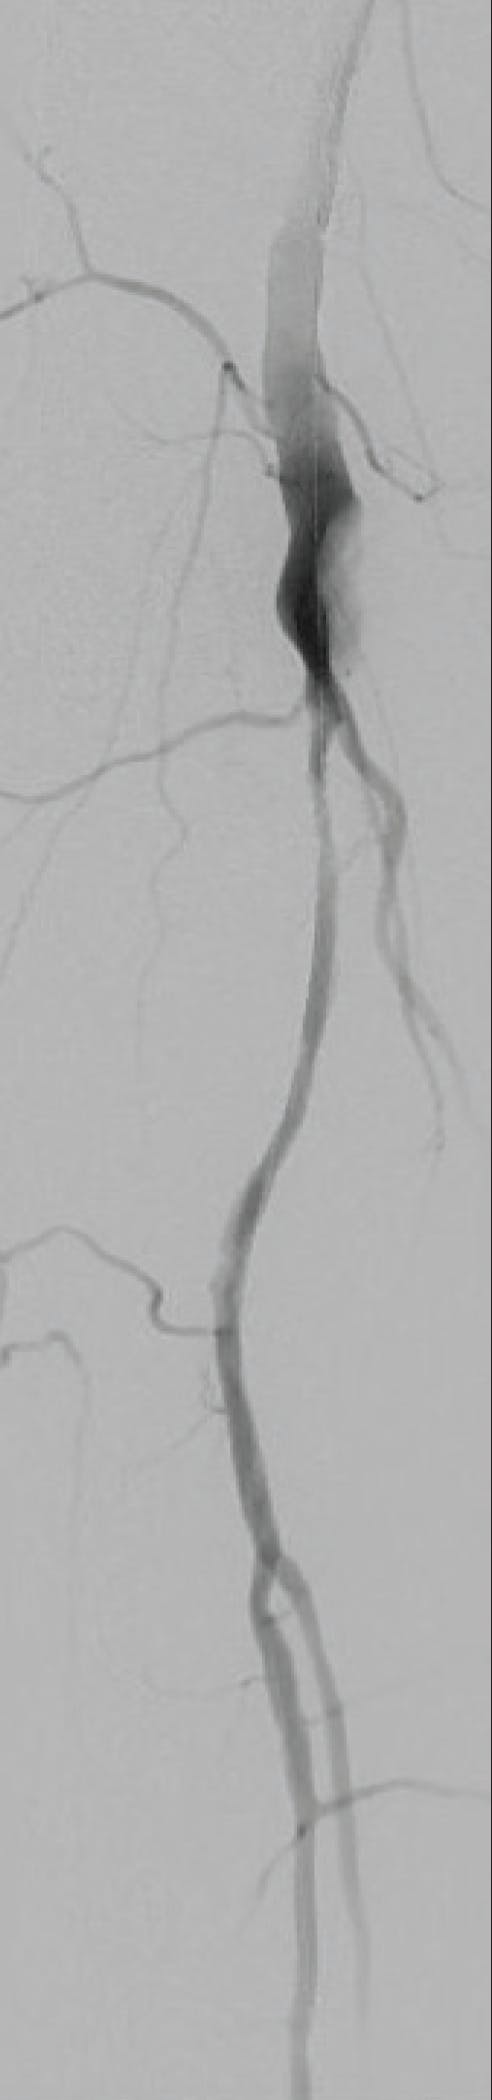

A man in his early 70s was admitted to the emergency department with right leg pain, pallor, and cold foot at the physical examination. The patient stated he had been kneeling for a long time during the days prior to presentation. The patient had a history of hypertension, hyperlipidemia, and tobacco use, and he had a history of right popliteal aneurysms that were treated with Viabahn 8- X 100-mm and 7- X 150-mm stent grafts (Gore & Associates) in 2018. A duplex ultrasound and CT scan showed occlusion of the popliteal right stent graft and anterior tibial artery, as well as a poor runoff on the distal posterior tibial artery.

TREATMENT OPTIONS

Due to the ischemic symptoms, anticoagulation was not considered an option. Therefore, it was decided that a Fogarty catheter thrombectomy under fluoroscopic guidance would be used for the procedure to allow selective access to the distal tibial vessels. After multiple failed clot extraction attempts with the Fogarty, CAVT was performed with Lightning Bolt 7 as a bailout procedure, which resulted in a successful and effective outcome.

PROCEDURAL DETAILS

A right surgical, proximal, superficial femoral artery access was performed. A subsequent angiography through a 8-F sheath showed in-stent occlusion above the knee (Figure 1A). Initially, an over-the-wire Fogarty Thru-Lumen Embolectomy catheter (4- and 5-F) (Edward Lifesciences) was used. After that, a 0.018-inch guidewire was advanced through the occlusion (Figure 1B). After multiple attempts without thrombus extraction (Figure 1C), and angiography that showed no progress on thrombus burden, Lightning Bolt 7 was advanced into the stent graft (Figure 2A), starting aspiration proximal to the clot with restoration of lumen patency. After three passes through the stent, there was the reappearance of tibioperoneal trunk and anterior tibial artery, without signs of peripheral embolization (Figure 2B). The procedure was completed using proximal stent deployment on superficial femoral artery stenosis (8 X 79 mm Omnilink [Abbott]) and a kissing balloon angioplasty of the posterior tibial artery and peroneal artery (2.5 and 3 X 40 mm).

Figure 1. Angiograms showing occlusion of the right popliteal stent graft (A) and thrombectomy with an over-the-wire Fogarty catheter (B) without thrombus extraction (C).

Figure 2. The Lightning Bolt 7-F catheter was advanced proximal to the thrombus (A) and lumen restoration was successful (B).